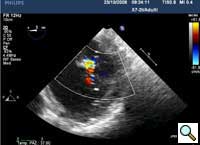

In absence of controlled clinical trial data which are forthcoming from the EVEREST II randomized study, the indications for the MitraClip therapy are currently based on registry experience and will evolve as the technique improves, experience is growing and the data to demonstrate efficacy and safety becomes available. At this time, the best indication for the MitraClip therapy is for symptomatic patients with clinically significant functional or degenerative MR who are at high or increased risk for open heart surgery. From a pure technical standpoint, the procedure so far has only been demonstrated in a subgroup of patients with specific anatomical characteristics which are summarized below and shown in Figure 3. Anatomic suitability is assessed by transesophageal echocardiography, and mitral regurgitation should originate from the central portion of the valve involving the A2-P2 segments, since the device is not ideal to work in the commissures at this time; the mechanism of MR can be either a prolapse/flail or MR due to restricted leaflet motion unrelated to rheumatic disease; the separation between the two leaflets at the site of regurgitation should be limited; severe annular dilatation and/or severe calcification should be absent or is relevant. In case of flail, the flail segment width should be less than 15 mm, and the flail gap less than 10 mm. Figure 4 is a 3D echo image of a patient with posterior leaflet prolapse selected for MitraClip therapy. In case of functional MR, the leaflets should have a minimal residual tissue available for coaptation with the MitraClip device. Figure 5 shows 2D color Doppler jet extension over the coaptation line at TEE short axis transgastric view, while Figure 6 shows the tenting area and the coaptation depth of a patient undergoing MitraClip implant.